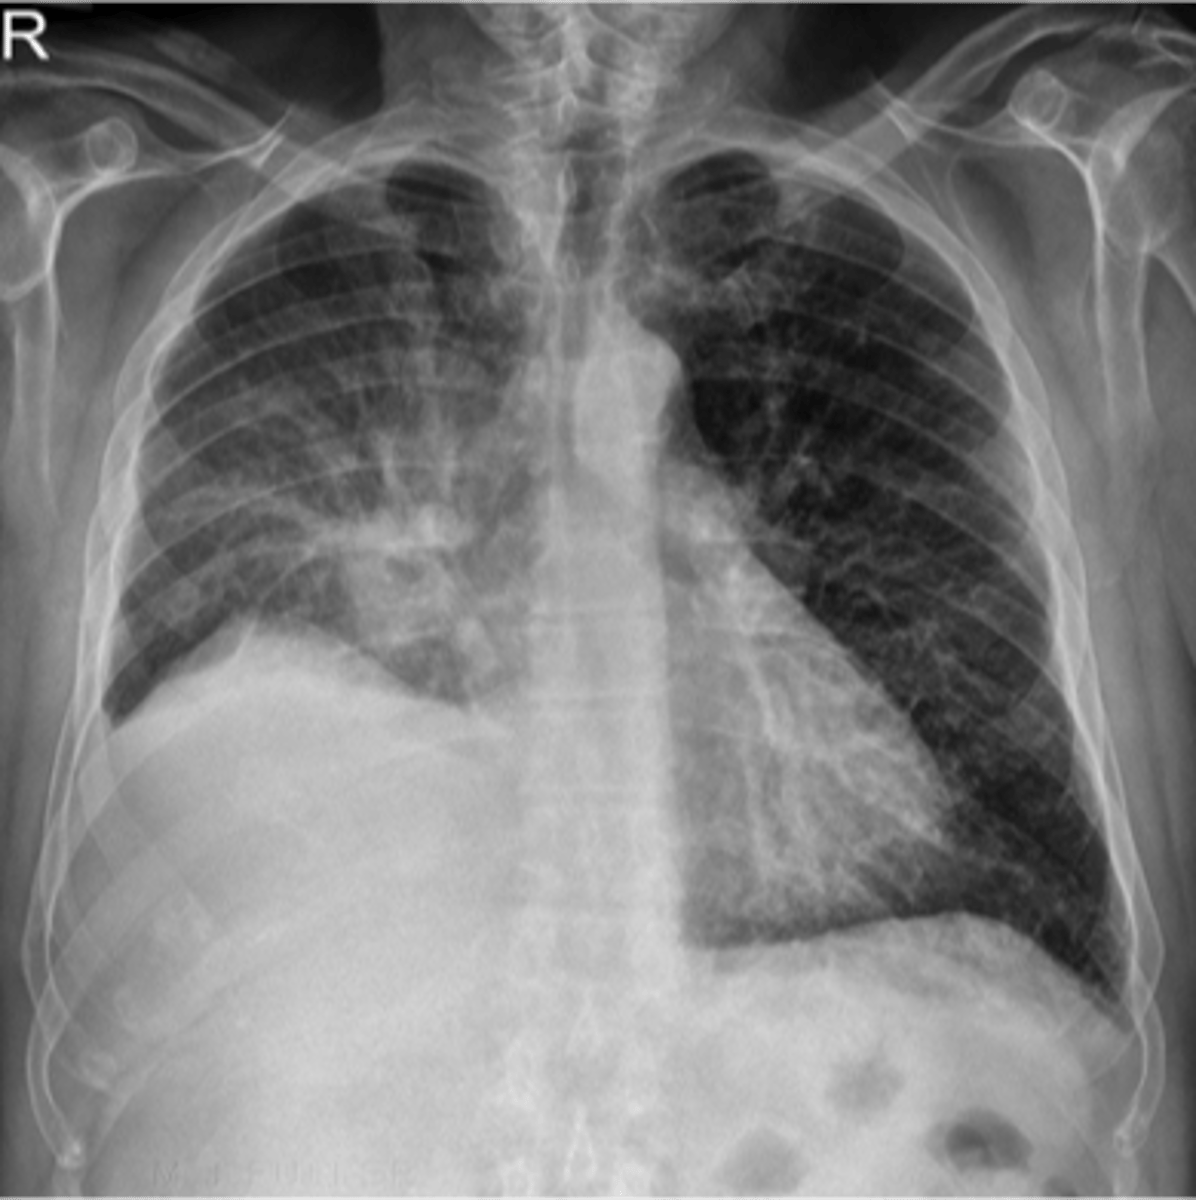

Bilateral pleural effusion